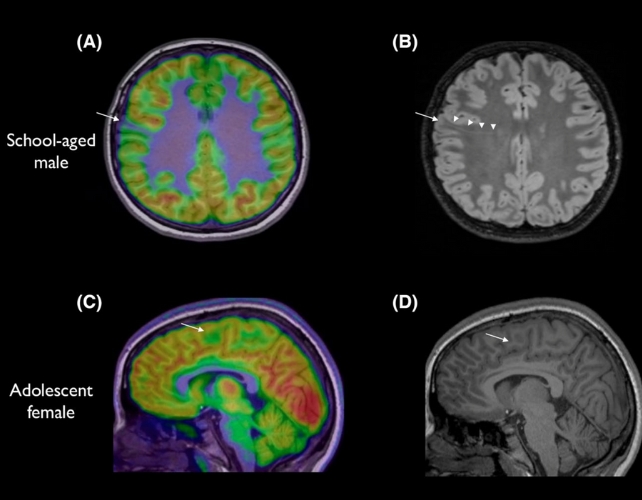

A team led by Emma Macdonald-Laurs, a paediatric neurologist at the Royal Children's Hospital in Melbourne, trained an AI tool on child brain images to find lesions the size of a blueberry or smaller.

Of the patients who took part, with conditions known as cortical dysplasia and focal epilepsy, 80 percent had previously had an MRI scan come back as normal.

When the researchers used the AI tool to analyse both MRI and another type of medical scan called a PET, its success rate was 94 percent for one test group and 91 percent for another.